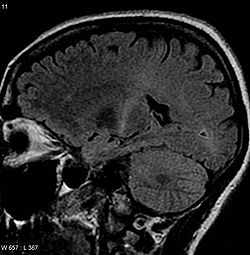

La Sla, sclerosi laterale amiotrofica, la terribile malattia senza cura e scampo, ha colpito solo in Piemonte, in questi ultimi anni, 123 contadini, di cui ben 20 giovani, sotto i 30 anni.

Non a caso, infatti, la devastante patologia neurodegenerativa che provoca l’irreversibile perdita di motoneuroni è anche chiamata il male di Lou Gehrig, il giocatore americano di baseball morto nel 1941di Sla.

E a rincarare la dose una recente ricerca scientifica – denominata Phytomer – dell’INSERM (National Institute of Health and Medical Research), presentata a maggio a Parigi, ha accertato che gli agricoltori, i viticoltori in particolare, possono subire una perdita delle capacità cognitive e disabilità cervello, a causa del contatto con limitate dosi di pesticidi.(articolo di Le Monde)

Il 50% dei vigneron seguiti dallo studio ha manifestato effetti significativi del deterioramento delle funzioni cerebrali.